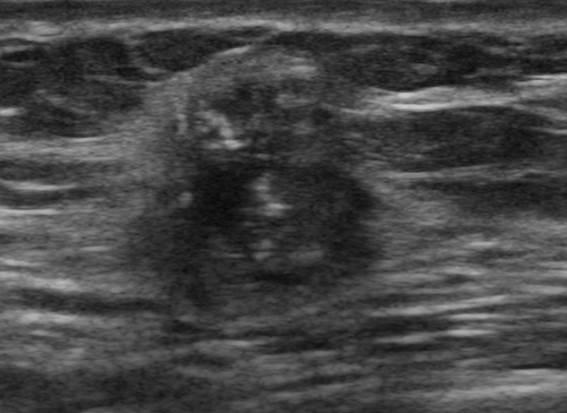

Ung thư vú

» Thông tin: Nữ giới – 41 tuổi.

» Lâm sàng: Khối tuyến vú.